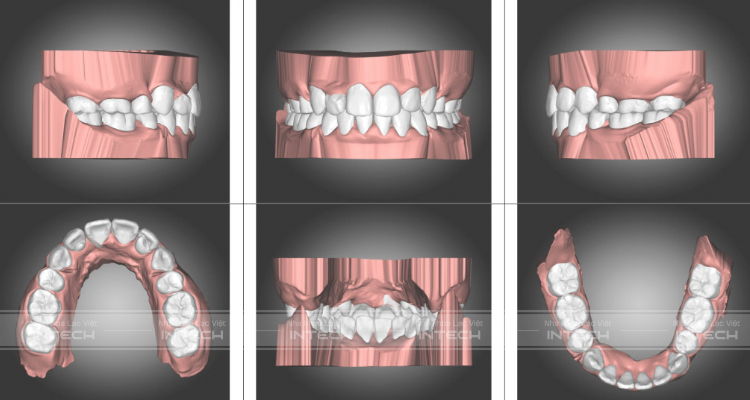

Mô phỏng tình trạng răng trước

Cùng phân tích tích trạng răng trước của bạn Đức Khải qua ảnh trong miệng, phim Panorama và Cephalo dưới đây:

- Chen chúc khấp khểnh cả hai hàm ở mức độ trung bình

- Răng cửa hàm trên bên trái bị mọc kẹt vào trong làm cho toàn bộ hàm trên bên trái bị xô sang bên phải khiến đường giữa hàm trên và hàm dưới bị lệch

Phần hàm trên bên trái có răng cửa có hình thể bất thường.

Đường giữa hai hàm răng lệch